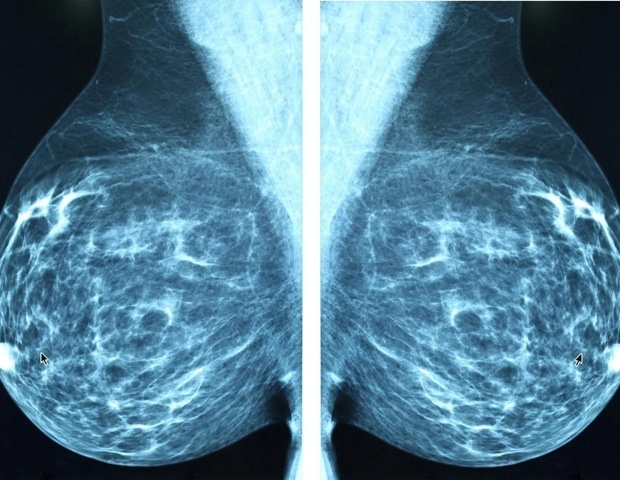

Μια επαναστατική προσέγγιση στη θεραπεία του τριπλά αρνητικού καρκίνου του μαστού

Ο τριπλά αρνητικός καρκίνος του μαστού είναι γνωστός ως μία από τις πιο επιθετικές μορφές καρκίνου. Η ονομασία του προκύπτει από την απουσία των τριών κύριων στόχων που καθιστούν άλλες μορφές καρκίνου του μαστού πιο θεραπεύσιμες με ισχυρές θεραπείες. Ερευνητές από το UCLA έχουν αναπτύξει μια νέα θεραπεία που θα μπορούσε να αλλάξει ριζικά την προσέγγιση στη θεραπεία αυτής της θανατηφόρας νόσου. Σε μελέτη που δημοσιεύθηκε στο Journal of Hematology & Oncology, η ομάδα περιγράφει πώς αυτή η νέα μορφή ανοσοθεραπείας, γνωστή ως θεραπεία CAR-NKT, μπορεί να επιτίθεται στους όγκους από πολλαπλά μέτωπα, ενώ ταυτόχρονα αποδομεί τις προστατευτικές τους ασπίδες.